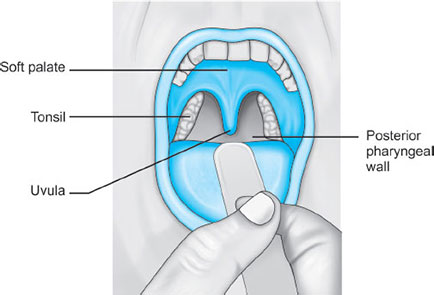

It starts below the soft palate, and extends to the superior edge of the epiglottis (Fig. 6).

Anterior wall is formed by the posterior third of the tongue.

During anesthesia or sedation with the patient in supine position, muscle relaxation + gravity = movement of base of the tongue toward the posterior oropharyngeal wall, causing airway obstruction. This is managed by use of oral airways or jaw lift.

The oropharynx opens to the oral cavity at the palatoglossal folds, marking the division between the anterior two-thirds and posterior one-third of the tongue. The palatoglossal folds make the fauces, which contain the tonsils.5

Hypertrophied tonsils can cause a challenge during mask ventilation or intubation.

Anterior to the fauces is the oral cavity proper, separated from the vestibule by the teeth and gums. Prominent or bucked maxillary teeth can interfere with laryngoscopy and intubation.